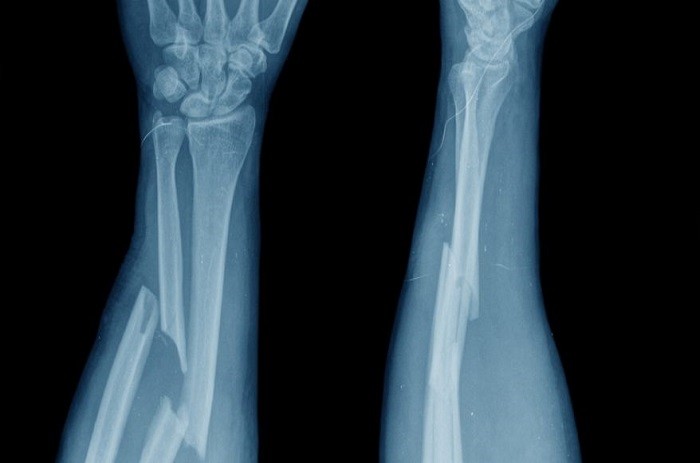

Referat Ocena ryzyka złamań patologicznych z wykorzystaniem technik cyfrowej analizy obrazu wygłosi: dr n. med. Piotr Biega, Katedra Fizyki i Inżynierii Medycznej PRz, Oddział Ortopedii Onkologicznej, Szpital Specjalistyczny w Brzozowie: Podkarpacki Ośrodek Onkologiczny